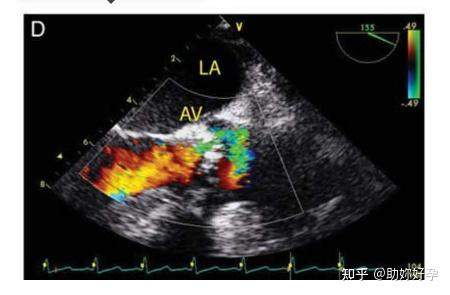

此外,多普勒信息也可以显示在类似于上述解剖结构成像的彩色窗口(彩色多普勒模式)中(图 9D)。彩色窗口的每一帧都由重复的超声波脉冲形成。每一帧包含多条扫描线,每条扫描线都有多个脉冲(称为 ensemble length)。每条扫描线需要这些重复的脉冲提供足够的信息,包括确定反射体的移动方向、反射体的平均速度、功率和方差(速度分布),因此帧率极低。帧频由下面的公式决定:

彩色多普勒成像的两个方面与时间分辨率有关:

①可以通过利用窄的彩色窗口来提高帧速率并因此提高时间分辨率。

②彩色多普勒能检测的最大速度可以被超声医师改变,这样脉冲重复频率会随之发生变化。降低能检测的最大速度和脉冲重复频率会降低时间分辨率,因此在检测较低速度时也会出现混叠。